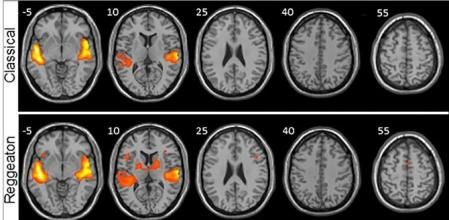

Después se sometió a las personas a una resonancia magnética funcional mientras escuchaban diferentes tipos y estilos de música sin letra, para estudiar de la manera más pura posible el procesamiento de la música. De no ser así, el lenguaje podría causar actividad cerebral pero empleando otras vías que no son las de la música.

Los investigadores analizaron el cerebro de cada participante anatómicamente y después la señal Bold, que es la que muestra qué áreas del cerebro cogen oxígeno y qué es lo que pasa cuando se activan las diferentes áreas.

Tras poner música electrónica, clásica, folch y reggaeton, el resultado fue increíble. El reggaeton fue el estilo musical que activó más áreas del cerebro, tanto las auditivas, como las que procesan el sonido, las motoras y las de movimiento. Según explica Martín-Fernández: "Es como si el reggaeton, con este ritmo peculiar y repetitivo, nos preparara para el movimiento, para bailar sólo de escucharlo", asegurando que este estilo musical utiliza los acuerdos de una manera predecible.

La música clásica, sin embargo, es mucho más compleja y mucho menos predecible, esto podría explicar porque es el estilo musical que activa menos las diferentes zonas cerebrales.